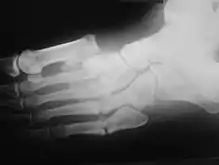

Oblique view X-ray in a 45-year-old male diabetic revealed a divergent, Lisfranc dislocation of the first metatarsal with associated lesser metatarsal fractures.

The same 45-year-old man with diabetes mellitus presented with a diffusely swollen, warm and non-tender left foot due to Charcot arthropathy. There are no changes to the skin itself.